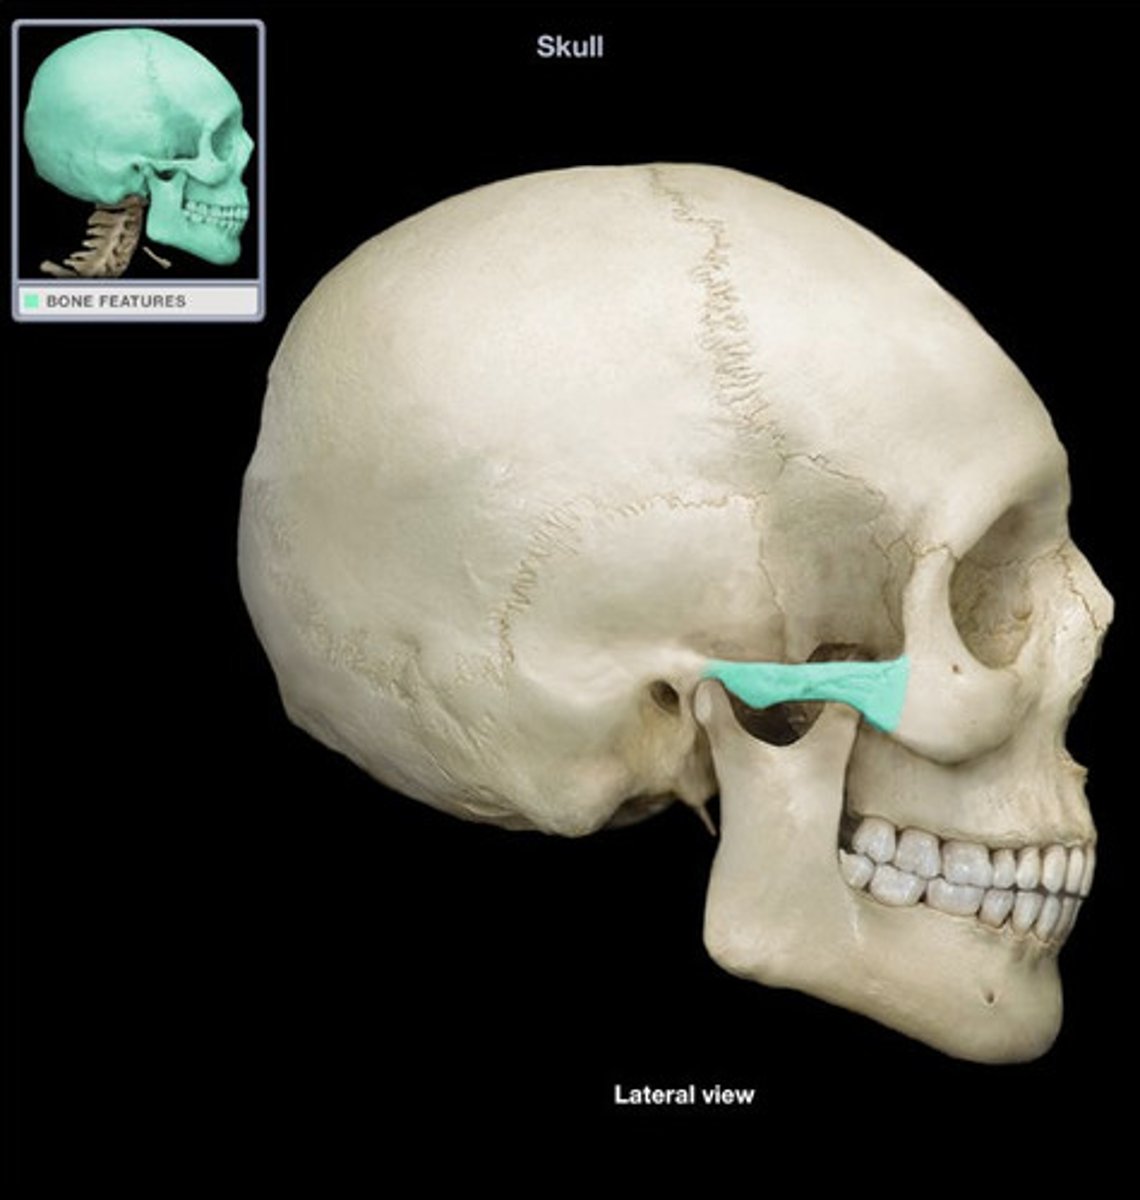

Zygomatic arch

Zygomatic process

Temporal process